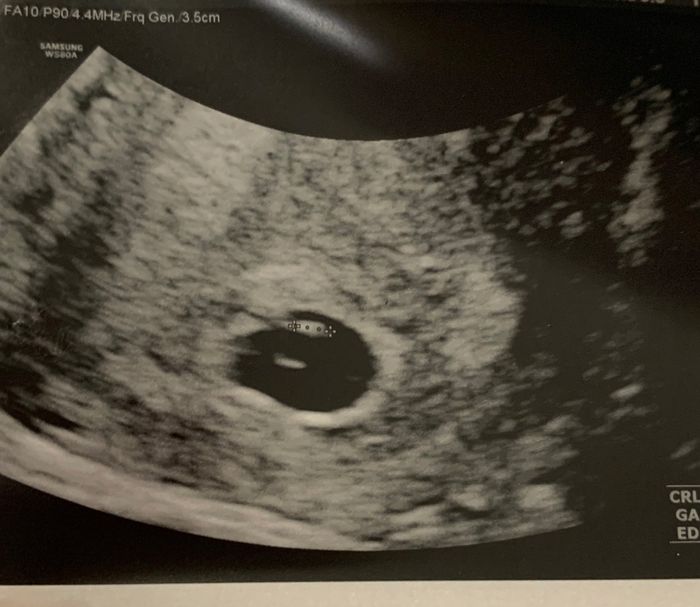

Future Mamme Giugno 2020Da Ermeni , Il 25 Novembre 2019 alle 12:26

Sono una futura Mamma di Giugno 2020♥️♥️♥️... non le aspettavo per domani, ma con un giorno di anticipo oggi ho fatto il test perché sono molto puntuale sempre 5-6 giorni...